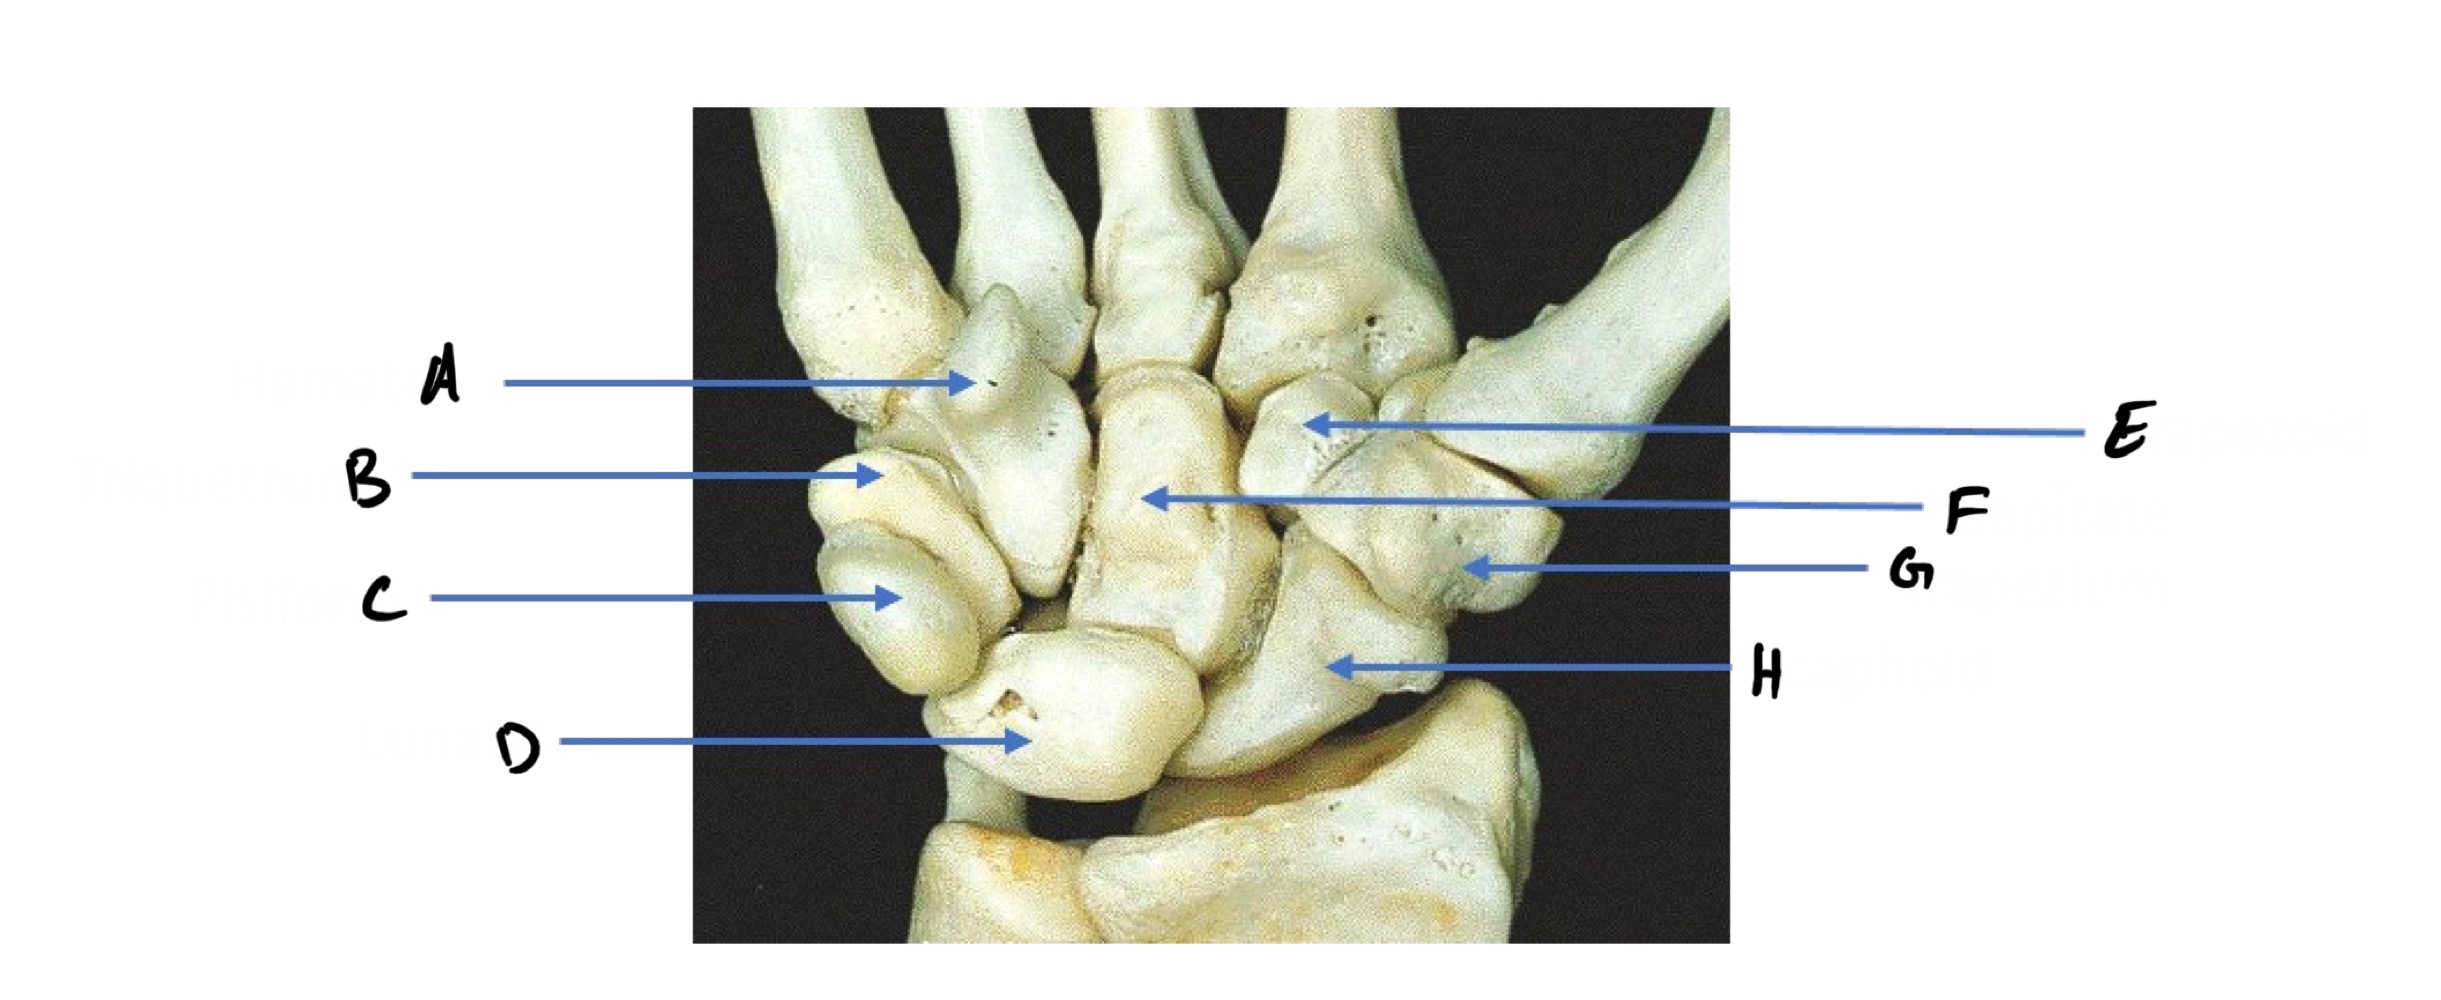

A

Hamate (Hammer shape)

B

Triquetrum

C

Pisiform (pea shape)

D

Lunate (like moon shape - lunar)

E

Trapezoid

F

Capitate (captain - biggest carpal bone)

G

Trapezium

H

Scaphoid